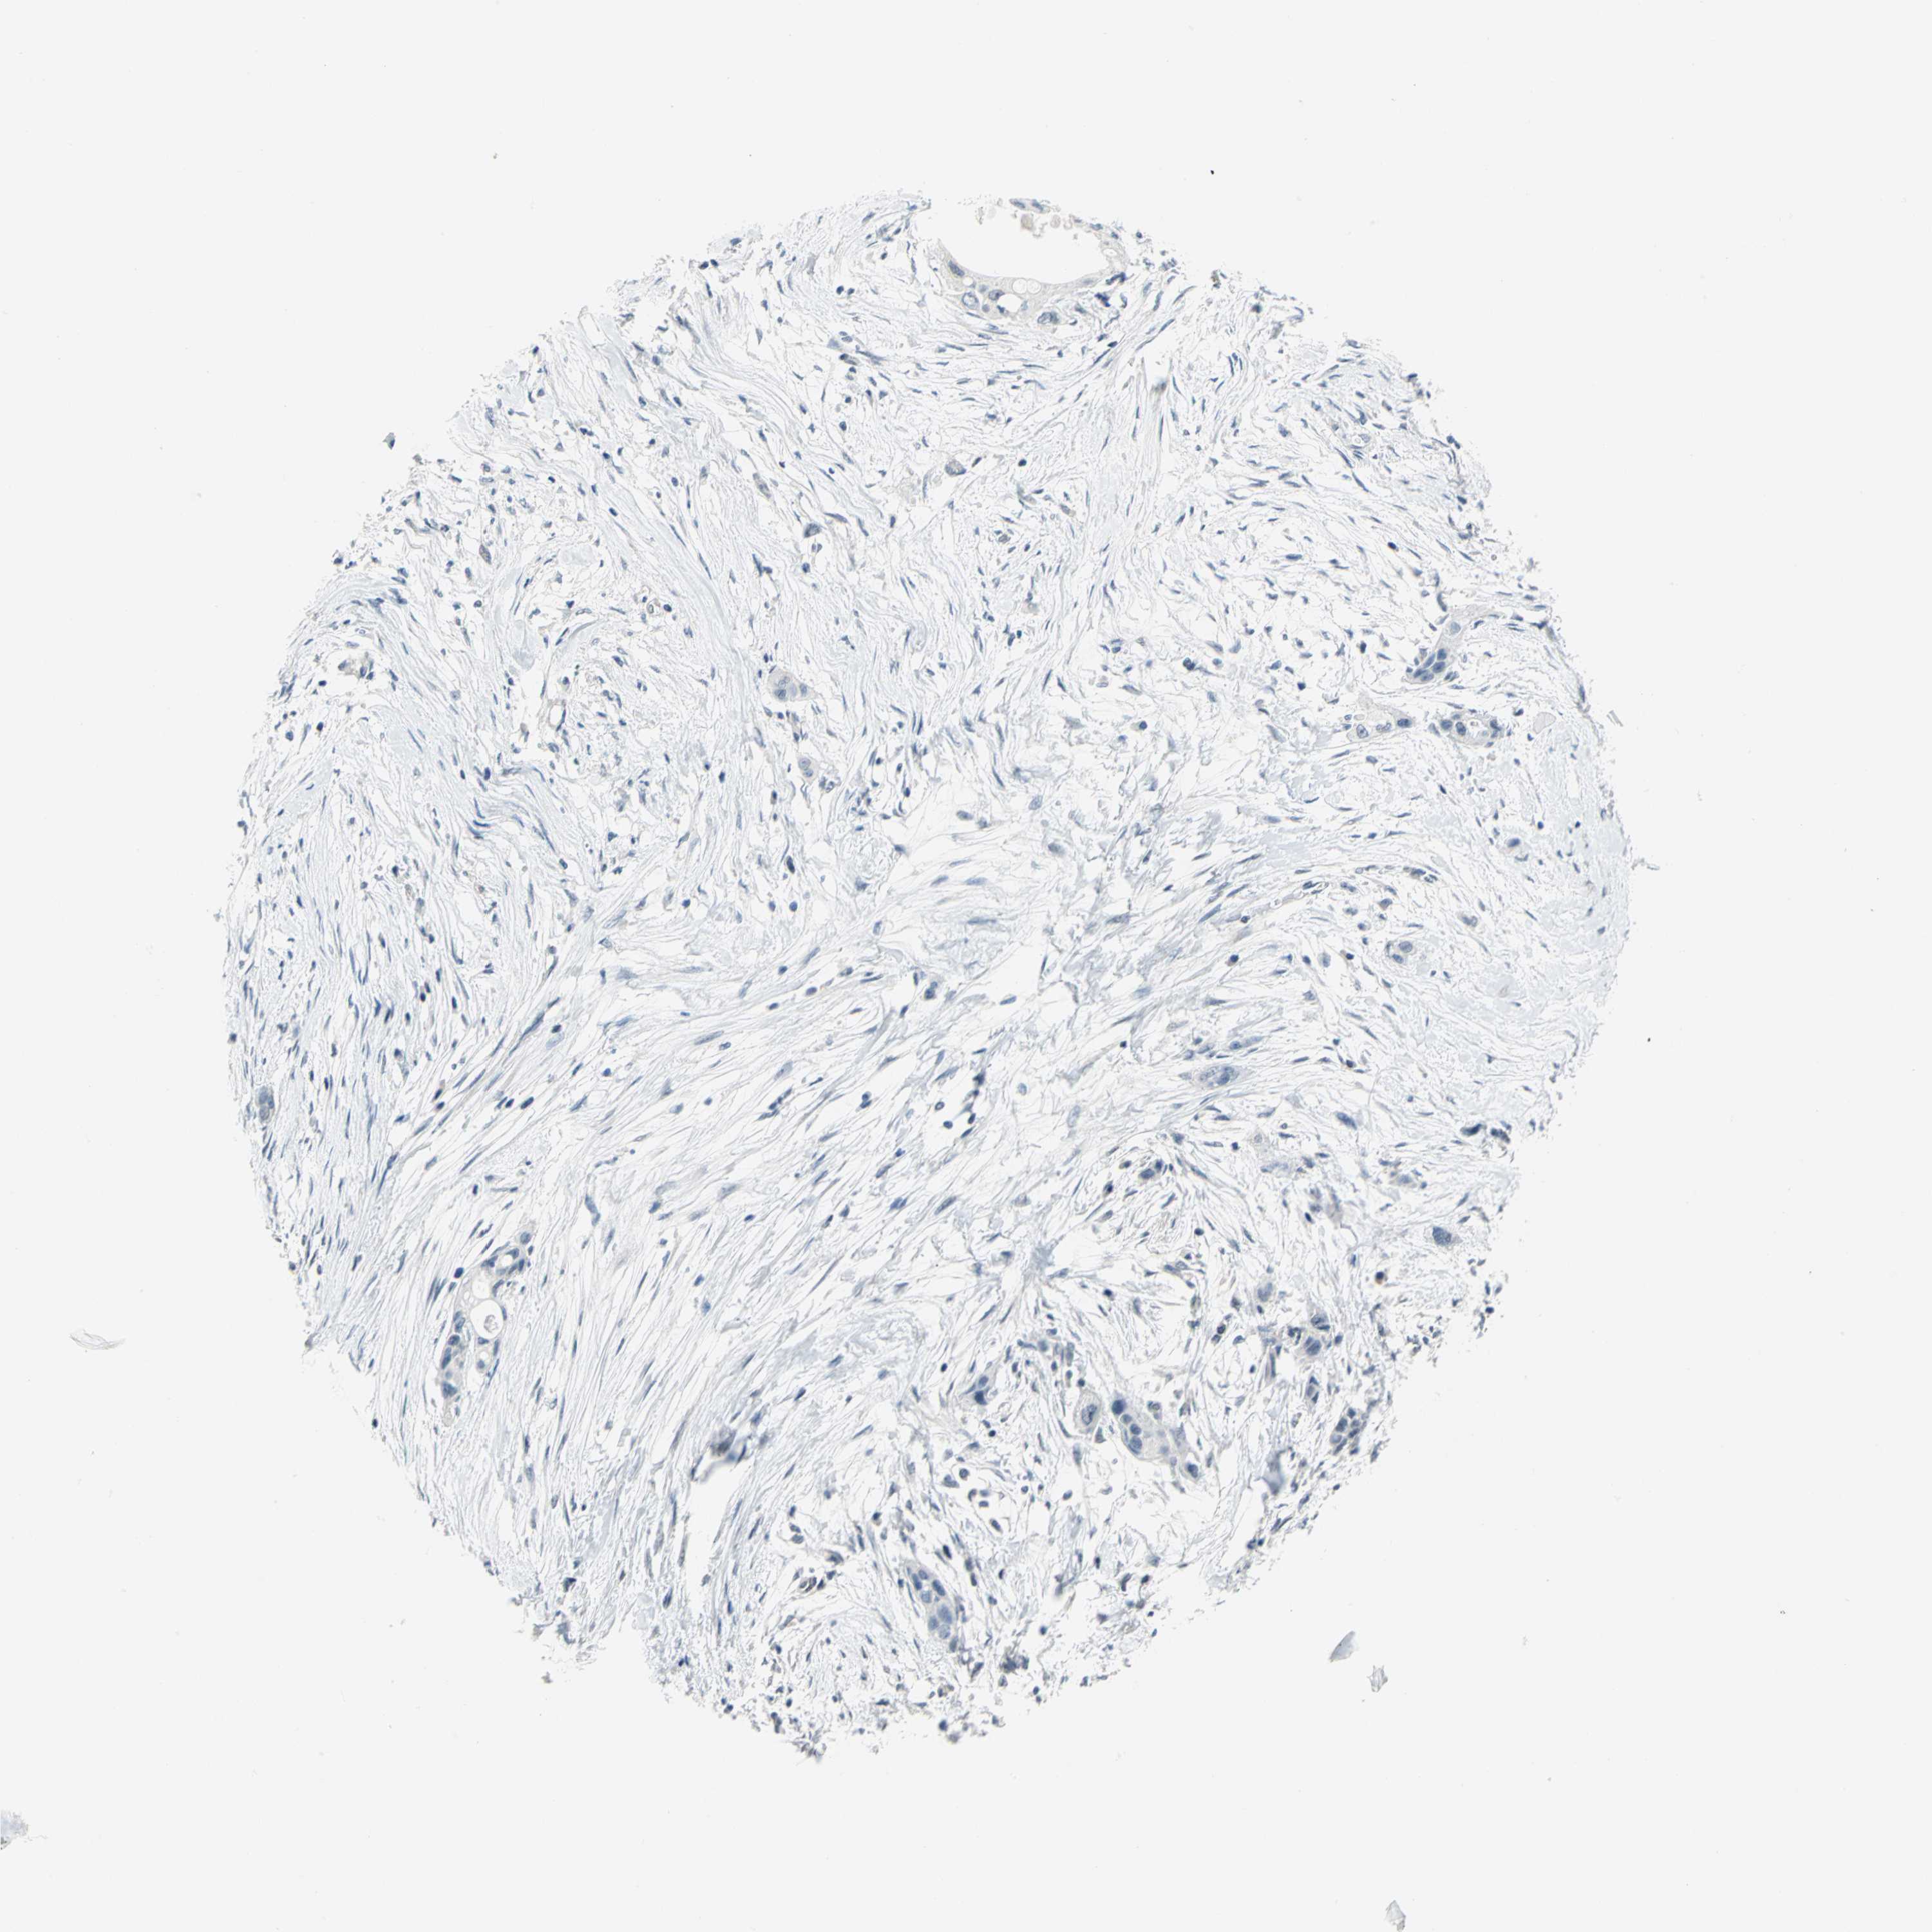

PANCREATIC CANCER - Protein expressioni

A mouse-over function shows sample information and annotation data. Click on an image to view it in a full screen mode. Samples can be filtered based on level of antibody staining by selecting one or several of the following categories: high, medium, low and not detected. The assay and annotation is described here.

Note that samples used for immunohistochemistry by the Human Protein Atlas do not correspond to samples in the TCGA dataset.

Antibody stainingi

Antibody staining in the annotated cell types in the current human tissue is reported as not detected, low, medium, or high, based on conventional immunohistochemistry profiling in selected tissues. This score is based on the combination of the staining intensity and fraction of stained cells.

Each image is clickable and will lead to virtual microscopy that enables deeper exploration of all samples and also displays staining intensity scores, fraction scores and subcellular localization as well as patient and tissue information for each sample.

Antibody CAB009326

Adenocarcinoma, metastatic, NOS